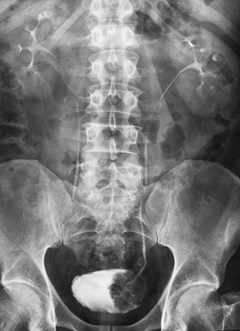

Так называют рентгеновское обследование почек, с помощью которого диагностируют опухоли, паразитарные заболевания, инородные тела и камни в почках и зачастую это первое обследование, которое назначают пациенту при подозрении у него патологий функции почек.

Обзорная урография дает возможность изучить состояние почек, начиная от верхних их полюсов и вплоть до начала мочеиспускательного канала.

Назначают обзорную урографию в тех случаях, когда необходимо дополнительно изучить кости скелета, тени почек, их форму и расположение, оценить общее состояние и функциональность других мочеполовых органов: мочевого пузыря, мочеточников.

Полученные после внутривенной урографии рентгенограммы отображают почки, лоханки и мочеточники, мочевой пузырь, предстательную железу. С помощью внутривенной урографии можно выявить опухоли, кисты, камни, расширения полостей почек (гидроуретер, гидронефроз), патологическое сморщивание и растяжение, гиперплазию тканей органов мочеполовой системы.